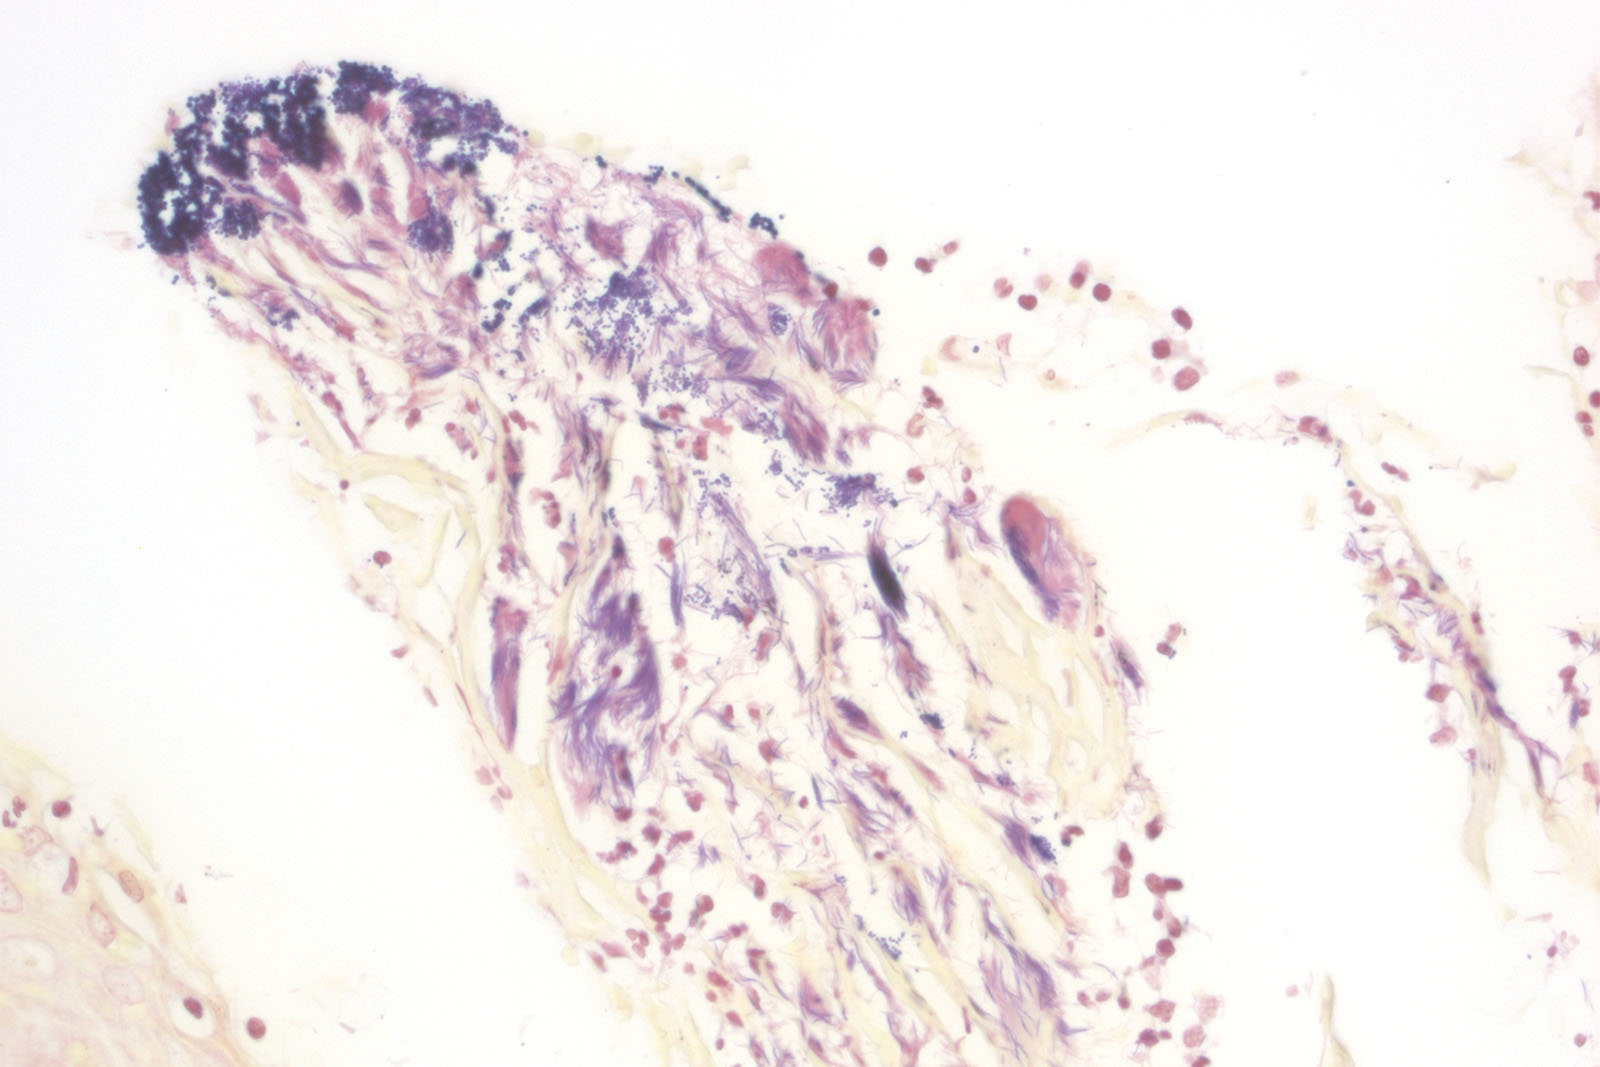

Gram staining is a method of differentiating bacterial species and it is commonly known and used in microbiology. It is also one of the most frequently used diagnostic methods in hospital and clinical laboratories. Gram staining differentiates bacteria into two groups: Gram-positive and Gram-negative. That division is based on the two groups’ bacterial membrane structural differences, i.e. their capability of retaining the dye. Gram-positive bacteria have a thicker cellular membrane which enables retaining the dye inside the cell by treating them with iodine solution that creates insoluble iodine and primary dye complex. Gram-negative bacteria have thinner cellular membrane structure which cannot retain the dye. It washes away through the membrane, and using counterstaining forms the basis for differentiating between the two bacteria groups. BioGnost’s BioGram Histo kit contains Gram Crystal Violet 1% solution, stabilized Gram Lugol solution, two packages of Gram Decolorizer 2 solution, Gram Safranin solution and two packages of picric acid in acetone. Its characteristics make it an optimal bacteria staining agent which provides consistent results.